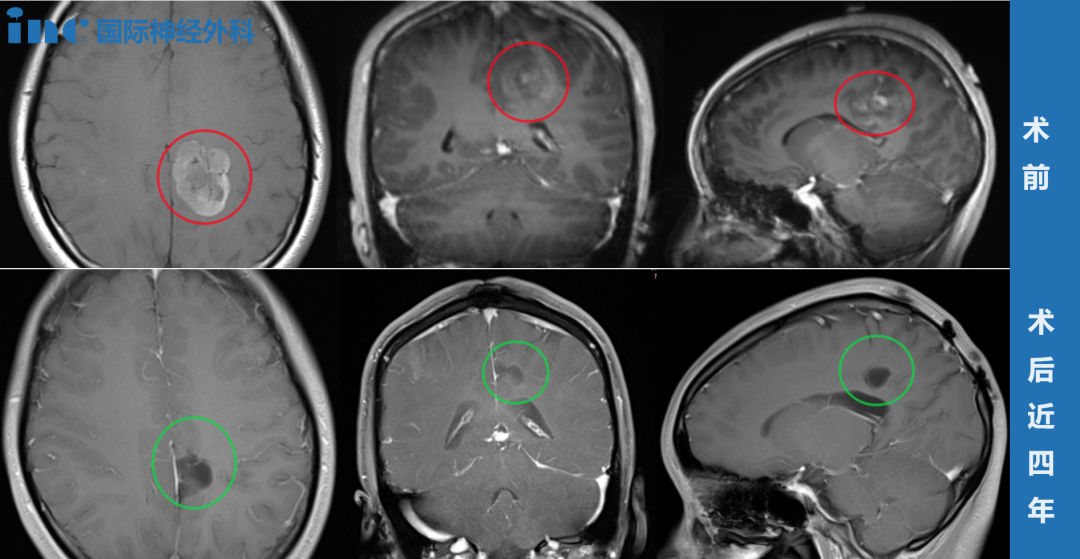

[案例] 反復(fù)癲癇發(fā)作竟是膠質(zhì)瘤惹的禍,全切手術(shù)4年后沒(méi)有復(fù)發(fā)、無(wú)癲癇再發(fā)

反復(fù)癲癇發(fā)作竟是膠質(zhì)瘤惹的禍,全切手術(shù)4年后沒(méi)有復(fù)發(fā)、無(wú)癲癇再發(fā)

2023-12-08 11:20:08